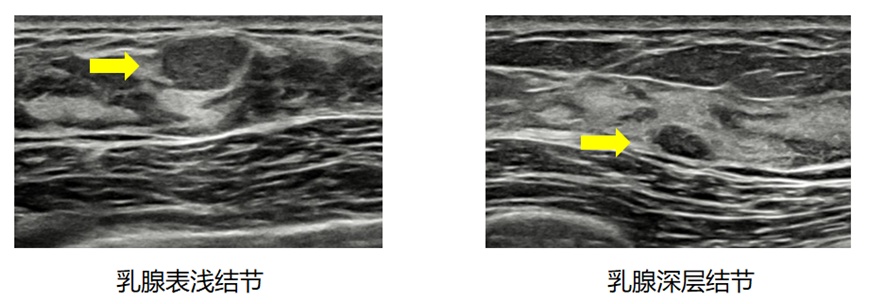

摸得到的块,可能长得位置比较表浅或者长得比较大;摸不到的块,可能长得位置比较深或者长得比较小,因此还是通过检查较为准确。

下面,我们继续通过两张图像的对比,让大家感受一下为什么有的块摸得着,有的块摸不到。

毕竟,夏天的薄被底下放颗黄豆你可能摸得到,冬天的厚棉被底下放颗红豆你就不一定摸得到了。

所以,依靠超声的检查,通过眼睛准确识别,比单纯的触诊会精确得多。就像你的痣长在某些犄角旮旯的地方时,不是特别大,你可能不一定会知道这里有颗痣,但如果照了镜子,就可以清晰地看到啦!